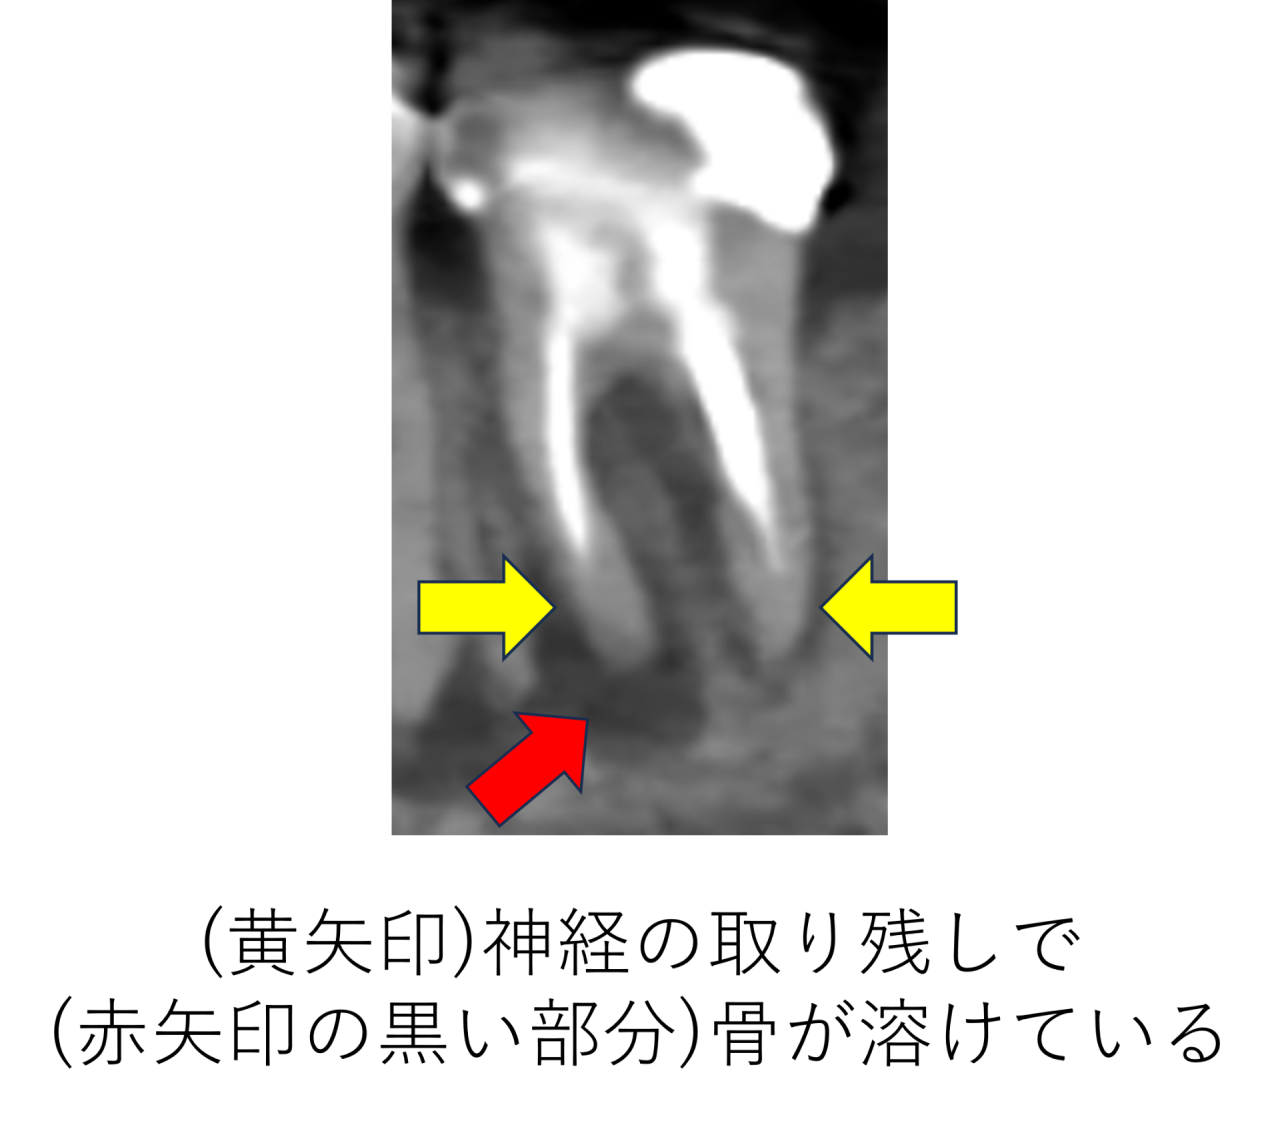

レントゲンを詳しく確認しました。横からの断面図を見ていくと、以前の治療で神経を取って薬をつめているのですが、神経の取り残しがあり、薬が根の先まで十分に入っていません。取り残された神経が腐ってしまい、根の中で細菌が繁殖し、根の外に出てしまい顎の骨を溶かしてしまっています。

前からの断面図を見ると、黒い部分が骨が溶けているところですが、とても広範囲にわたり骨が溶けているのがわかります。